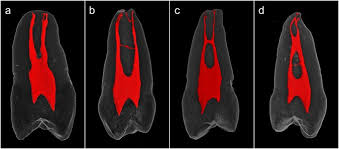

Alveolar bone proper/cribriform plate/lamina dura

A radiopaque layer of bone that lines the alveolar socket

alveolar bone proper (cribriform plate)

thin layer of bone that lines the socket and surrounds the root

has foramina that allow blood vessels from cancellous bone to connect with the vessels of the PDL space

Radiopaque or Radiolucent

PDL

radiolucent

lamina dura

radiopaque

alveolar bone proper